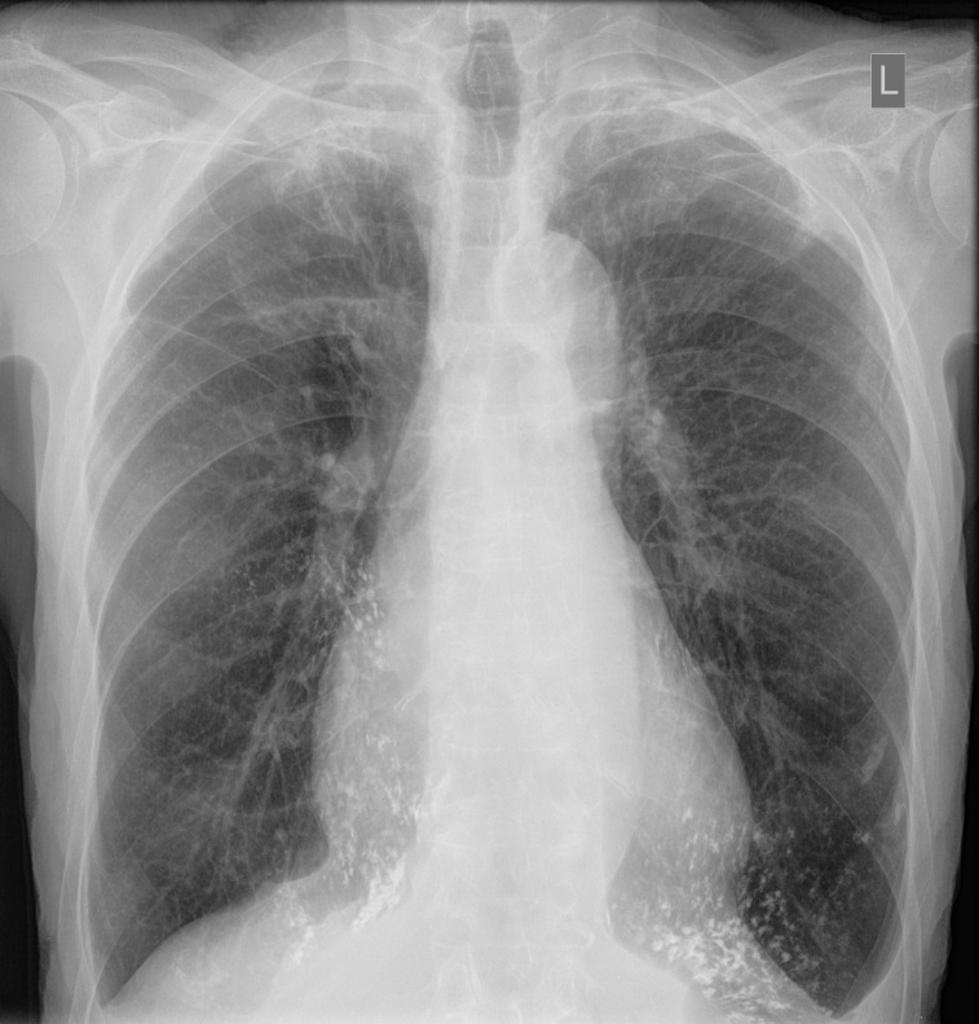

Where is the predominance of NSIP?

Lower lobes, posterior and peripheral predominance with sparring of the immediate subpleural spaces.

immediate subpleural sparing - a relatively specific sign

List the differences between NSIP and UIP:

NSIP:

UIP: